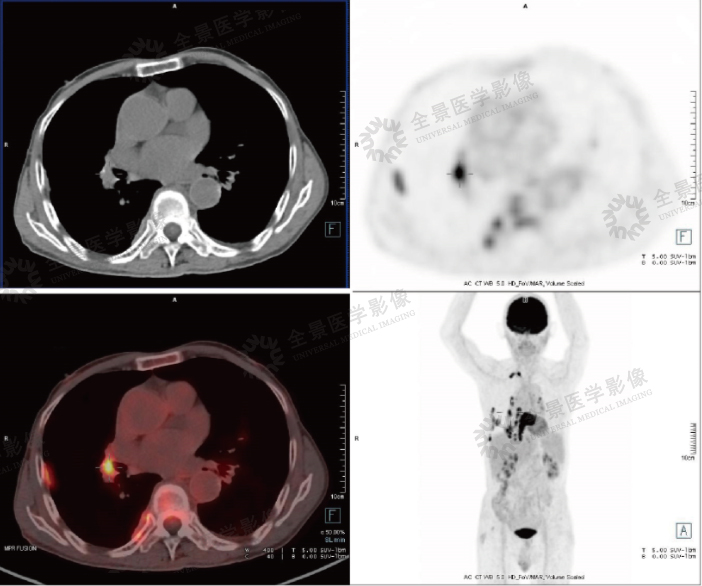

案例:老年女性,因体检发现纵隔占位。PET/CT提示右胸腔脊柱旁巨大囊实性占位伴实性区FDG摄取增高,相邻肋骨溶骨性骨质破坏。

结论:考虑神经源性肿瘤可能大,病理诊断富于细胞神经鞘瘤。